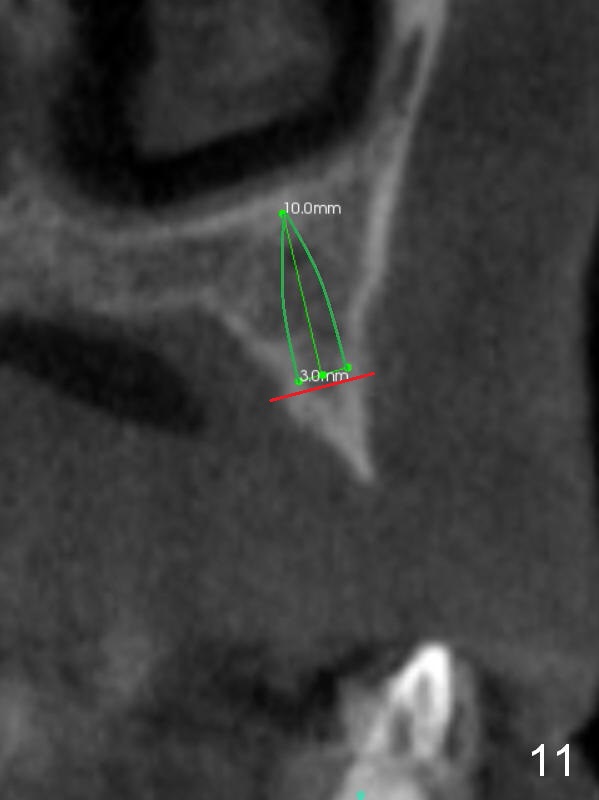

The ridge at #11 is similar to that at #10 (Fig.10), the treatment modality is the same (Fig.11,12). Comparison of the last 2 figures show that implant placement parallel to the palatal wall results in better trajectory for restoration.